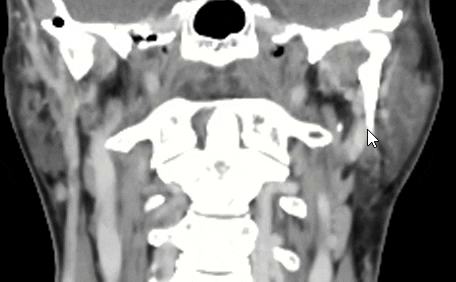

An animated gif with hyoid bone. Note the horns, left is quite lower than right.

I am also including some animated gifs of axial, sagittal, and coronal views of the calcification from the last CT scan.